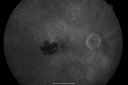

Retinal Vasculopathy associated with Facioscapulohumeral Muscular Dystrophy line os633 views59-year-old woman had a blood pressure spike to 170/90 and was on medications for that. She does have facioscapulohumeral muscular dystrophy, which runs in her family. She has a cousin with the same disorder.

VISUAL ACUITY: Her vision is 20/25 OU. IOP: OD 21, OS 18.

There is no posterior vitreous separation, telangiectatic vessels near the macula. There are patchy retinal hemorrhages. There is no edema or proliferation.